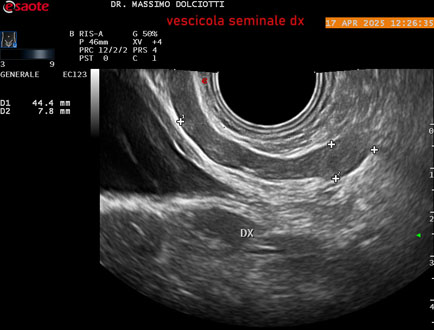

Data inserimento: 01/10/2025

Ecografia del: 17/04/2025

Strumento: Esaote MyLab Eight

Sonda: Convex Multifrequenza 1-8 MHz, Endocavitaria Multifrequenza 3-9 MHz e 3-13 MHz

Età Paziente: M 35 anni

Motivazione dell'esame: disuria.

Commento all'esame: le immagini ed il video documentano la prostata di ecostruttura regolare e morfovolumetria normale con diametro trasversale di 40 mm, diametro anteroposteriore di 21 mm e diametro longitudinale di 43 mm, con volume prostatico calcolato di 18 cc (v.n. < 20 cc), il profilo prostatico è regolare e netto, non si documentano calcificazioni intraghiandolari, la vascolarizzazione della ghiandola è normale. La vescicola seminale destra presenta diametro longitudinale di 44,4 x 7,8 mm, la vescicale seminale sinistra ha diametro longitudinale di 45,3 mm x 7,2 mm.

Conclusioni: prostata normale (normal prostate).